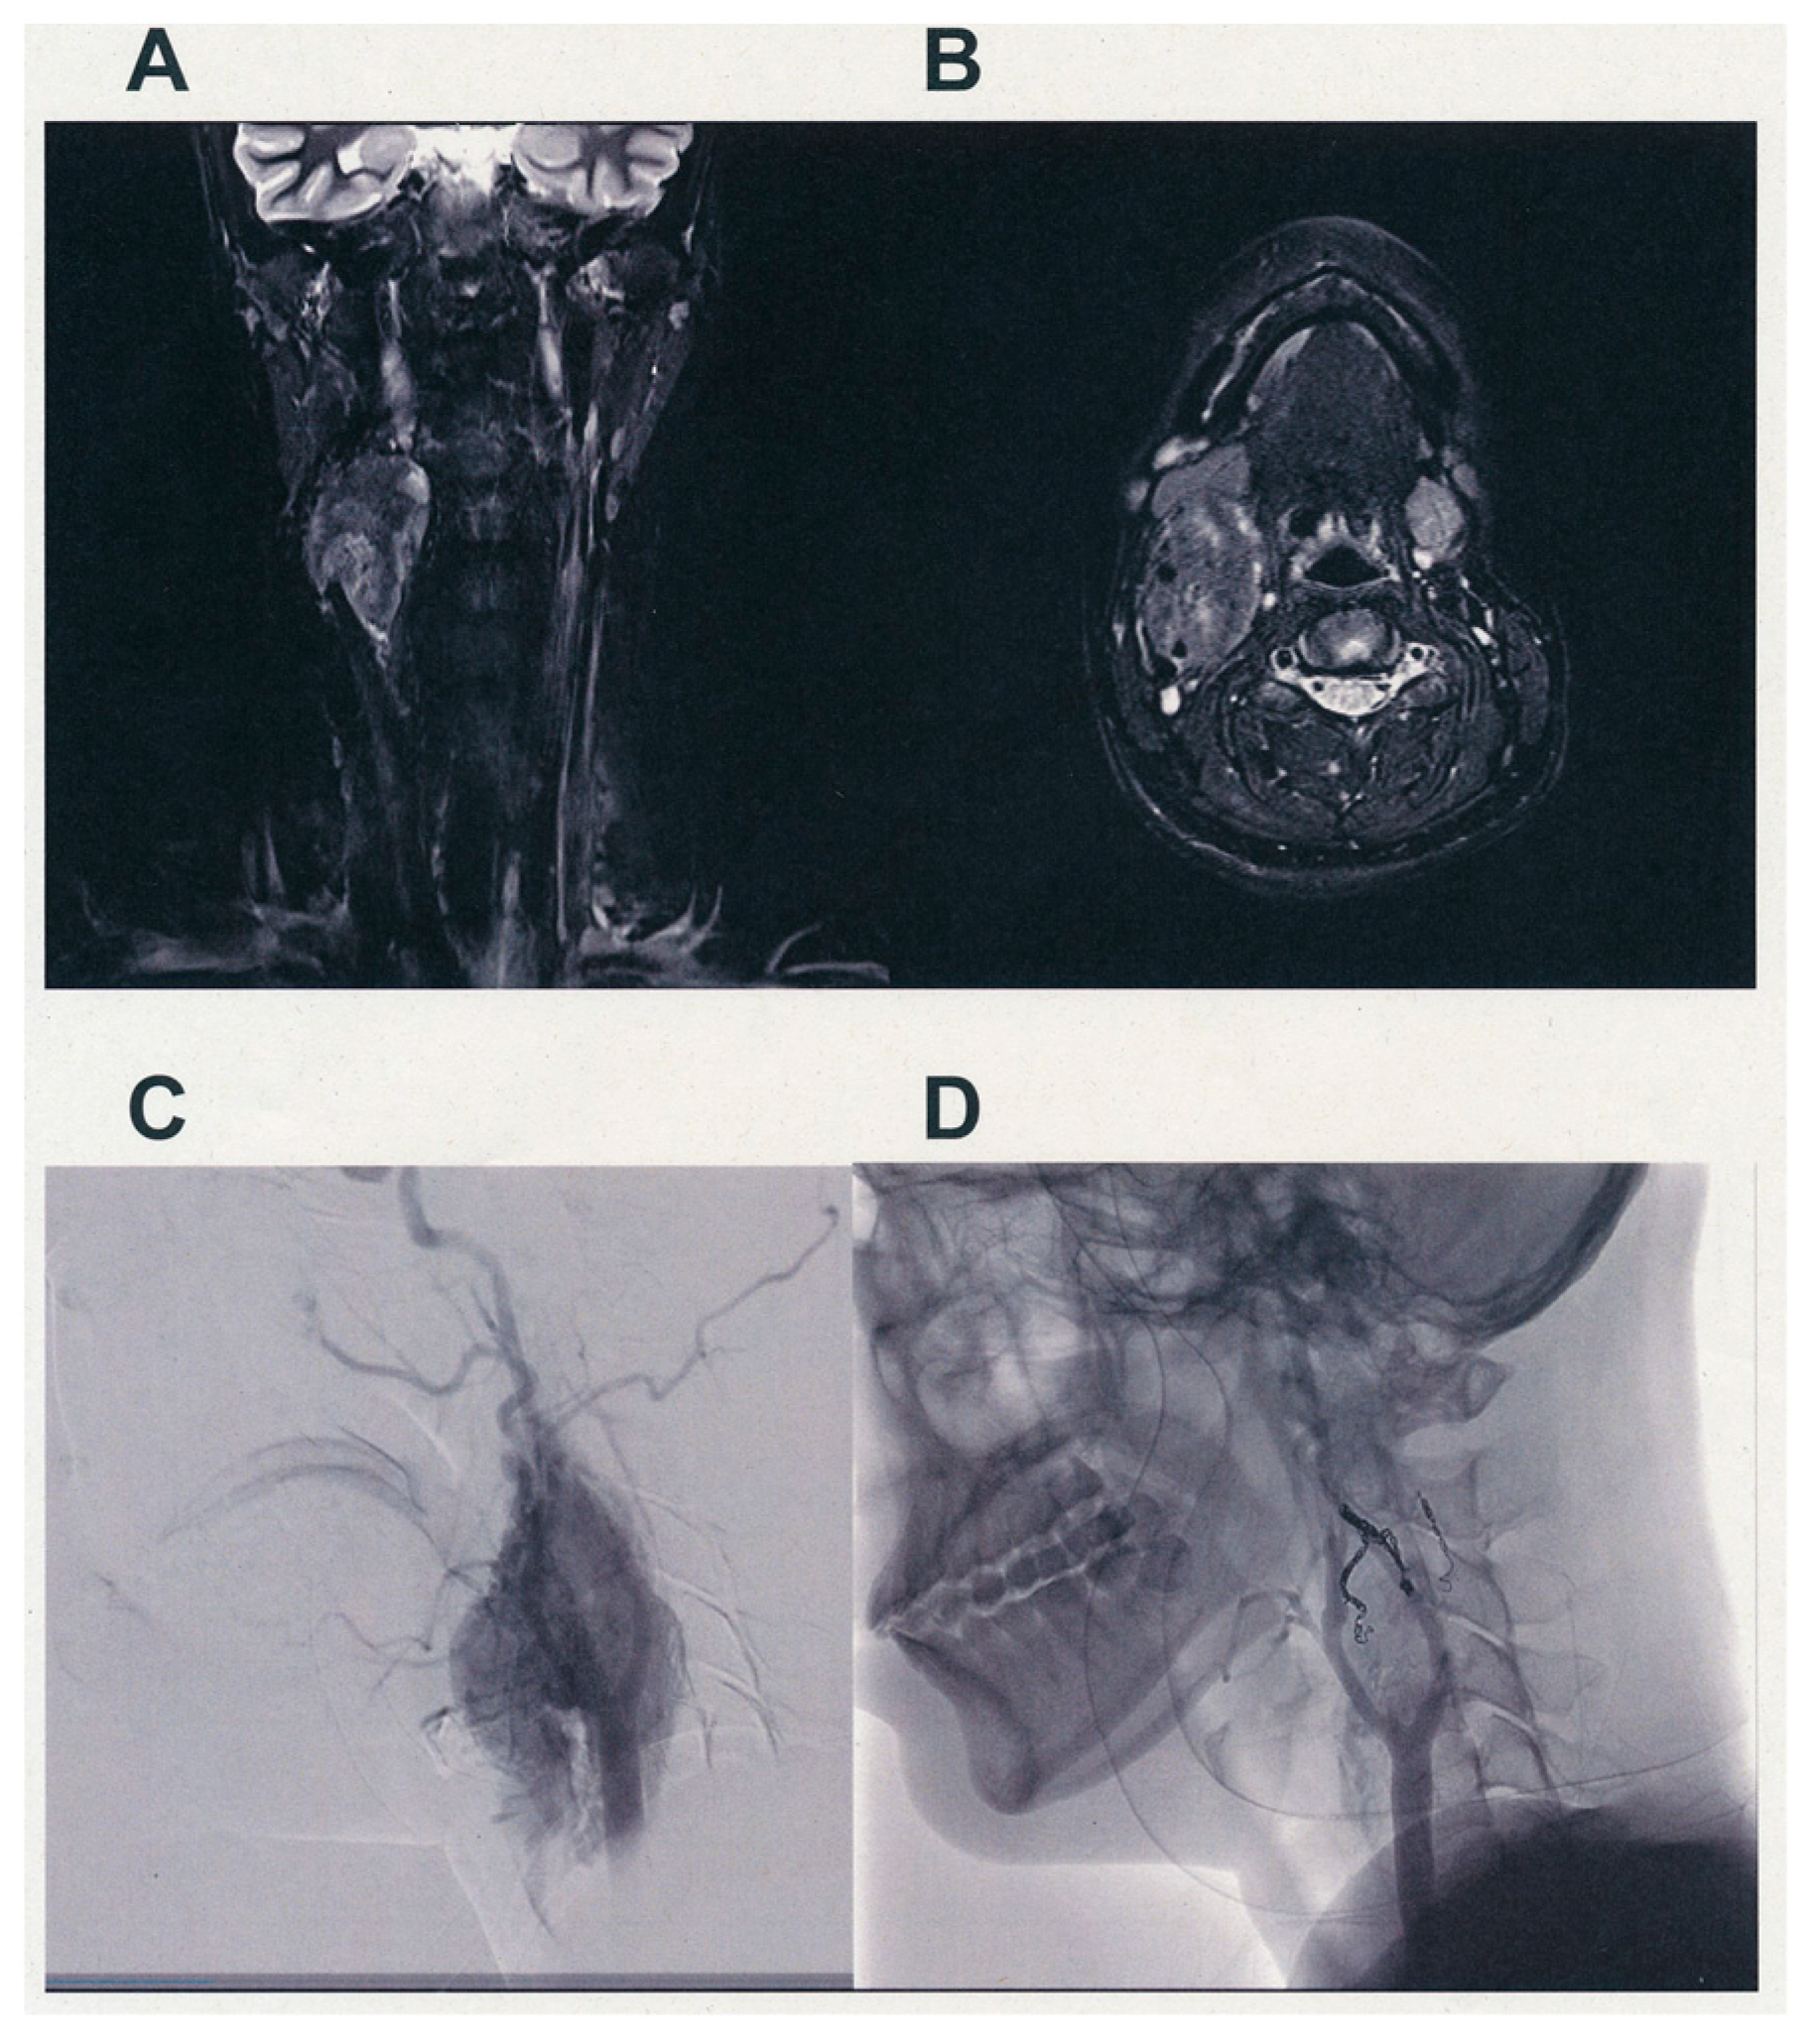

- Katagiri, K.; Shiga, K.; Ikeda, A.; Saito, D.; Oikawa, S.I.; Tsuchida, K.; Miyaguchi, M.; Tamura, A.; Nakasato, T.; Ehara, S.; et al. Effective, Same-Day Preoperative Embolization and Surgical Resection of Carotid Body Tumors. Head Neck 2019, 41, 3159–3167. [Google Scholar] [CrossRef]